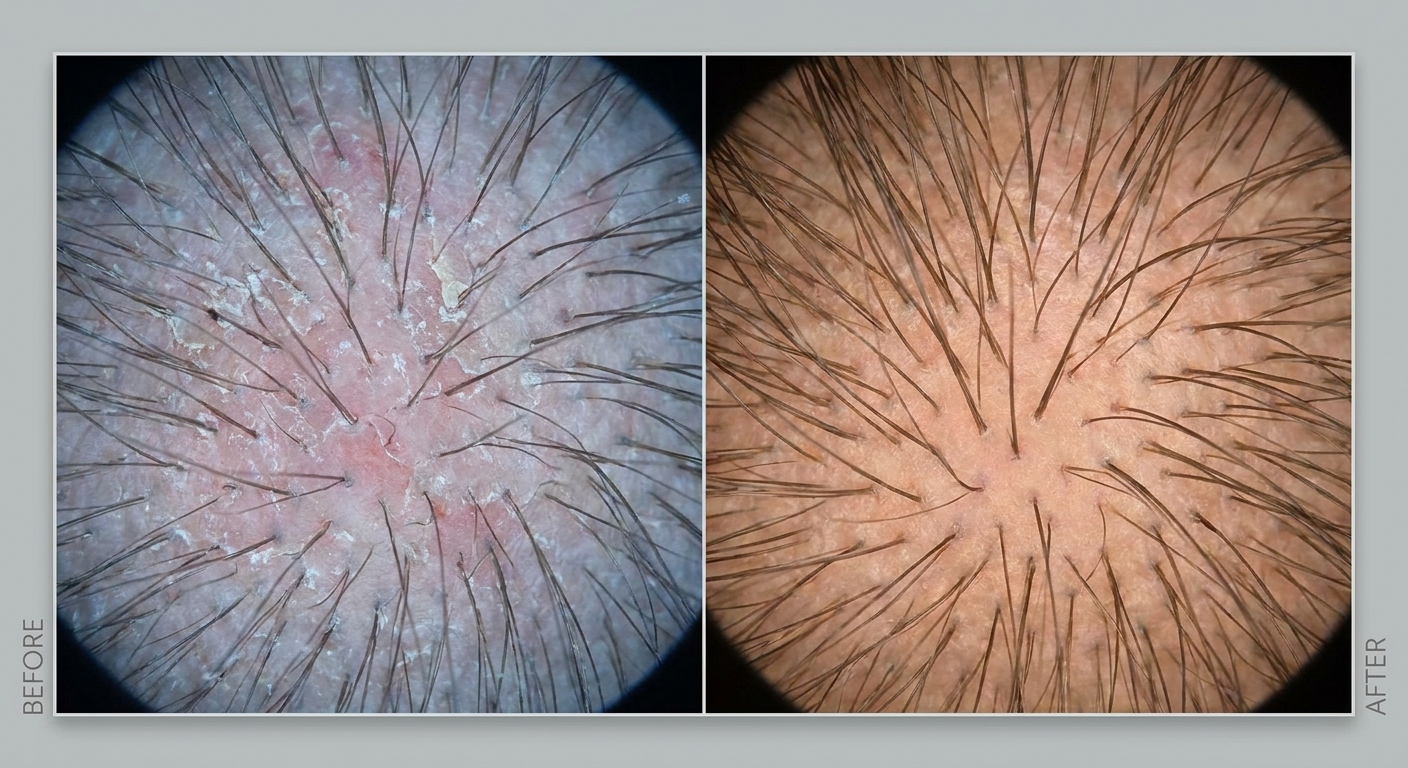

Widzisz swój skalp pod kamerą i wreszcie rozumiesz, co dzieje się z Twoimi włosami

Trychologia to nie stylizacja — to medyczne podejście do zdrowia włosów. Badanie trichoskopowe, szczegółowy wywiad, indywidualny plan terapii dopasowany do Twojego organizmu i budżetu.